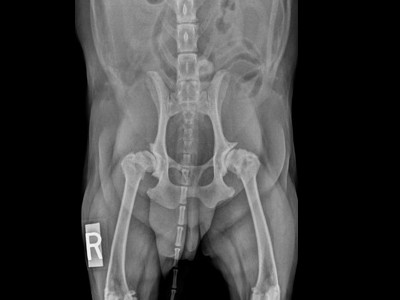

Tous les vétérinaires généralistes sont confrontés au quotidien à la gestion de ces animaux arthrosiques. Le programme de cette journée vous sera présenté par 5 conférenciers tous spécialistes dans leur domaine: Stéphane Bureau, Frédéric Meige, Nathalie Priymenko, François Gonneau et Thierry Poitte.

Objectifs pédagogiques de cette journée: être capable de:

- comprendre le procéssus arthrosique

- établir une démarche diagnostique face à un animal arthosique

- établir un protocole thérapeutique face à un animal arthrosique

- assurer le suivi thérapeutique de l'animal arthrosique

- connaître l'apport des médecines complémentaires dans le traitement de l'animal arthrosique.